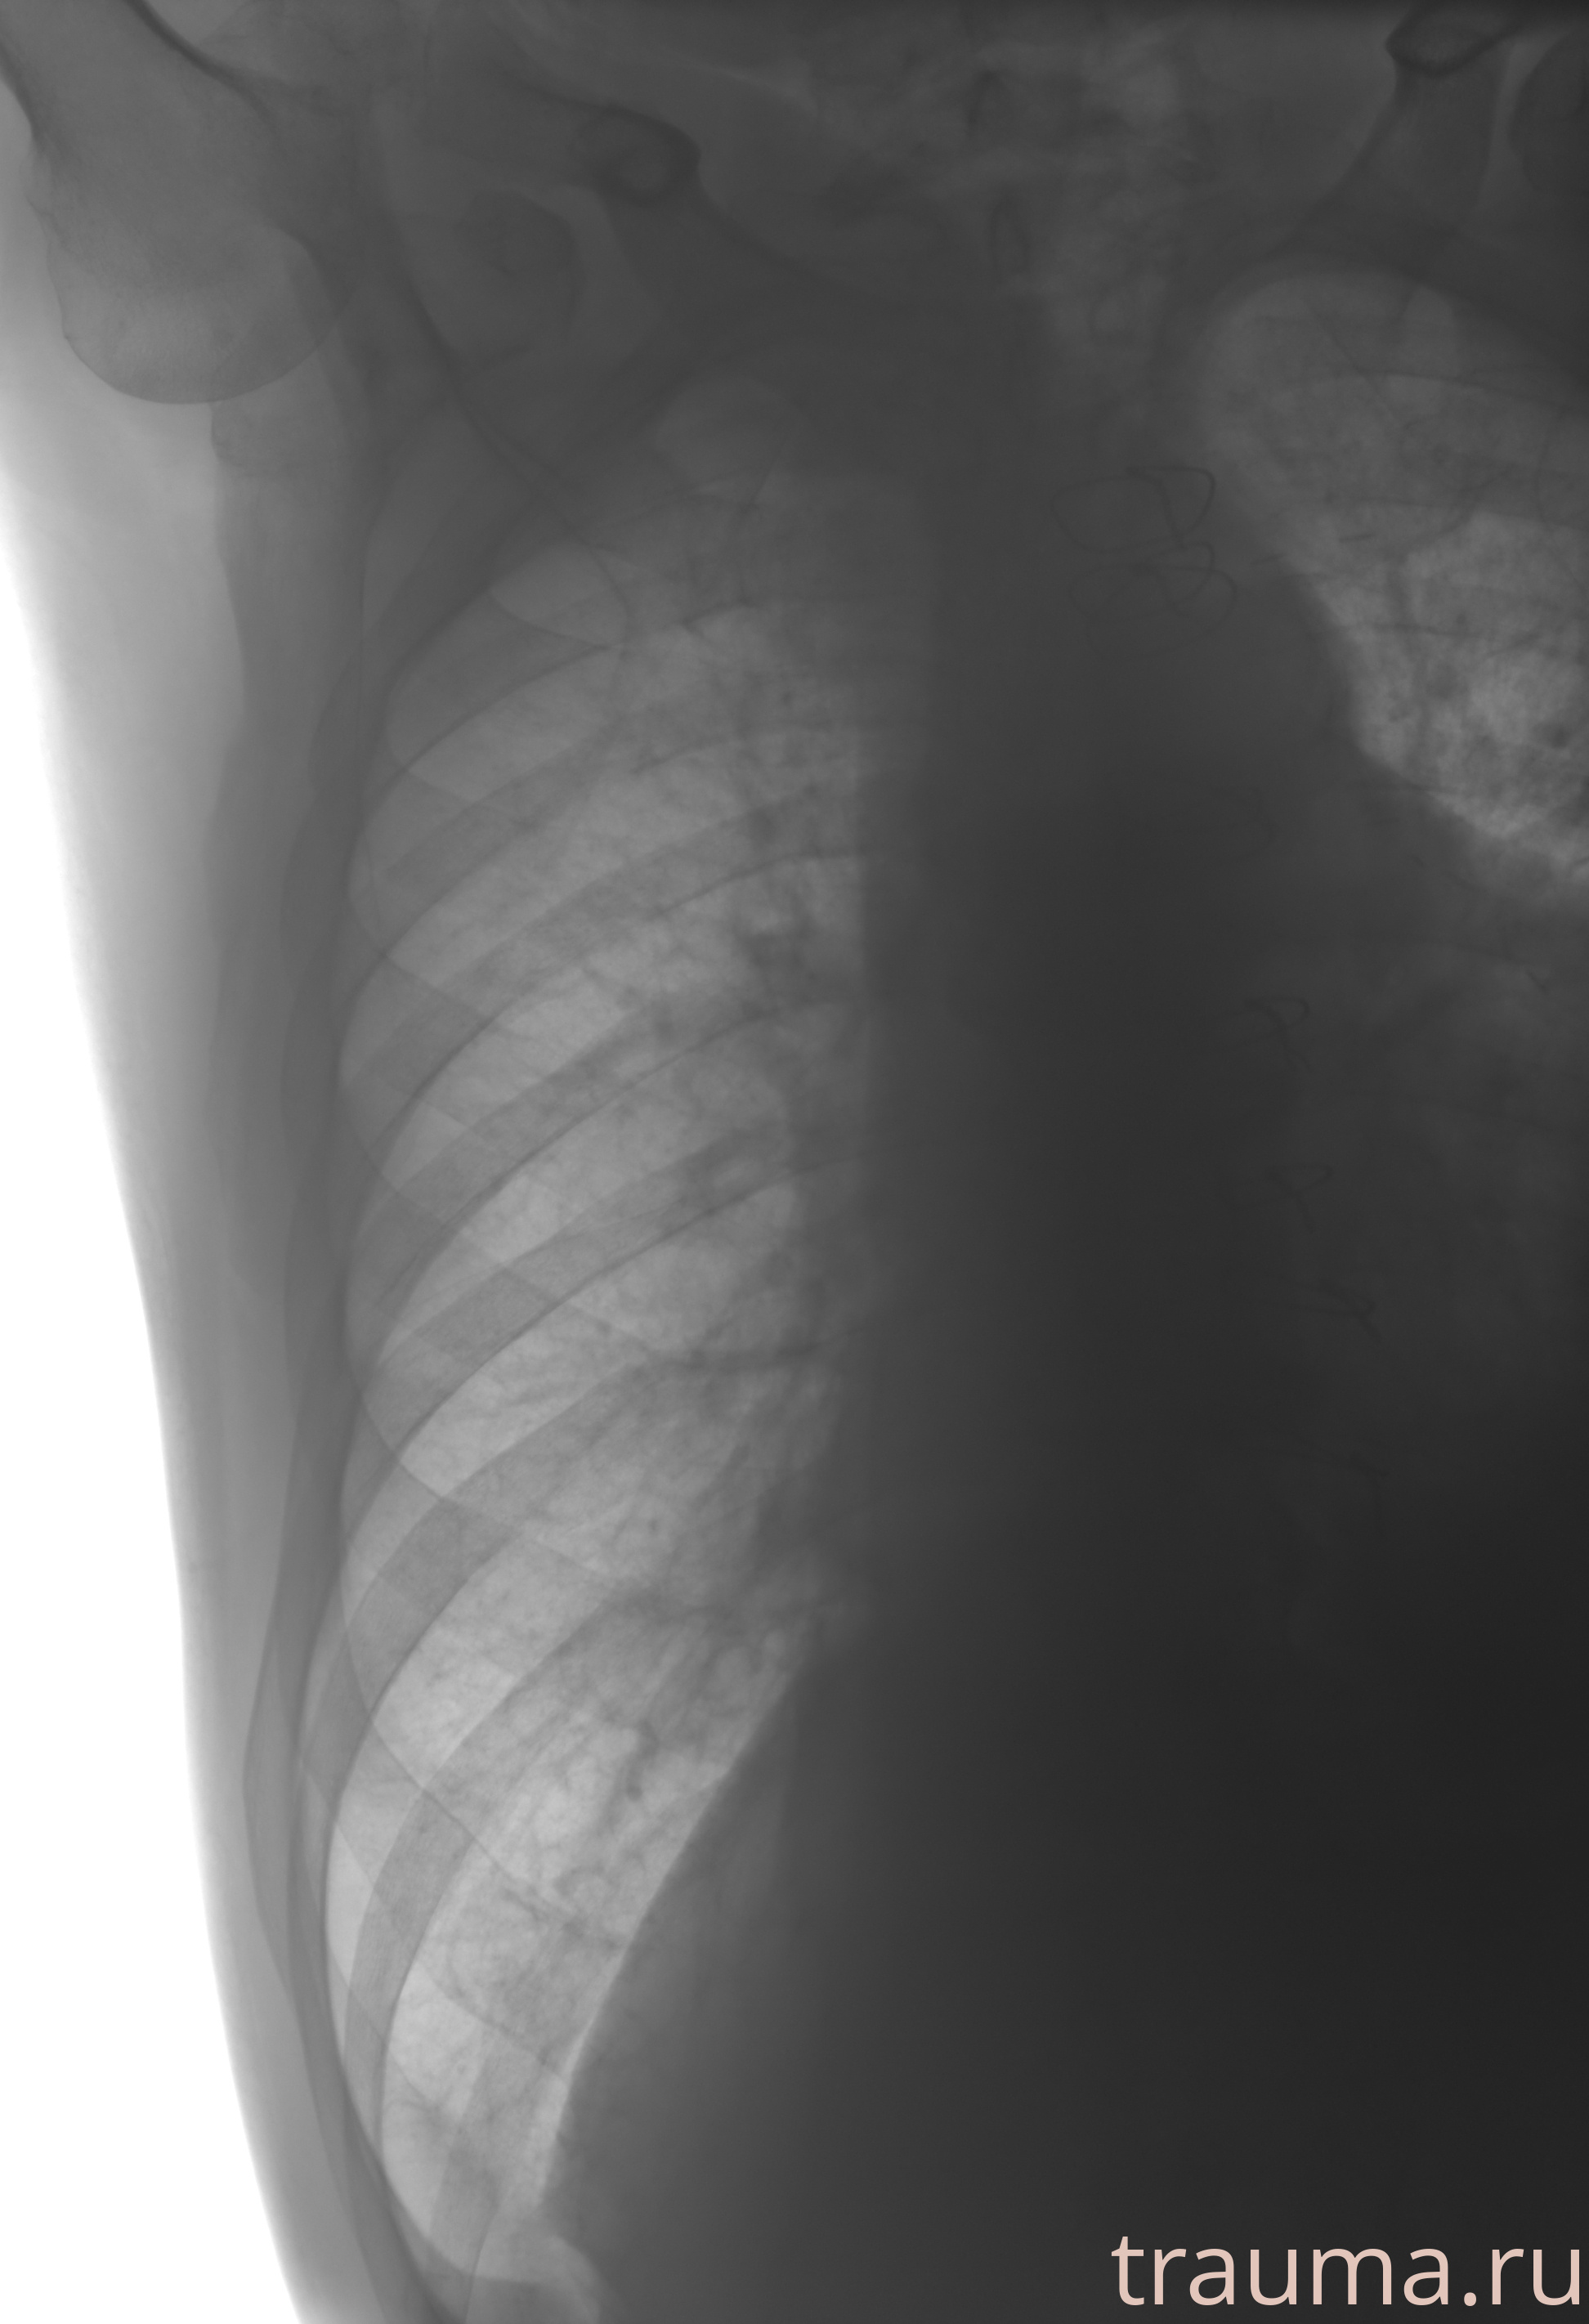

Рентгенограммы

Рентген на дому: по вашему адресу приезжает врач-рентгенолог, травматолог-ортопед с мобильным рентгеновским аппаратом, проводит диагностику травмы или заболевания, делает необходимые рентгенограммы, дает рекомендации по дальнейшему лечению. Получить качественные снимки в домашних условиях возможно благодаря уникальной методике, разработанной МосРентген Центром для института  Склифосовского